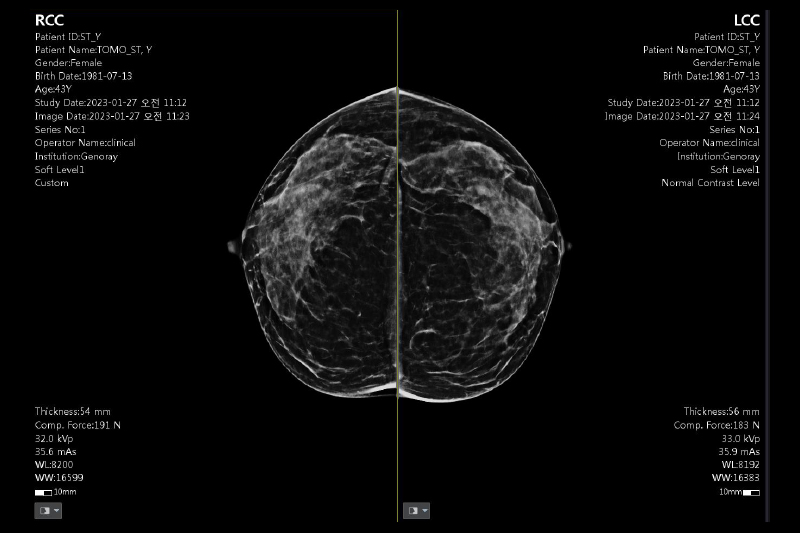

SYNTHESIZED 2D 기능

별도의 2D 촬영 없이 Tomo 촬영만으로 2D 영상 생성 가능한 SYNTHESIZED 2D 기능을 지원합니다.

CLINICAL IMAGES

오랜 경험을 통해 축적된 노하우로 진단영상을 제공합니다.